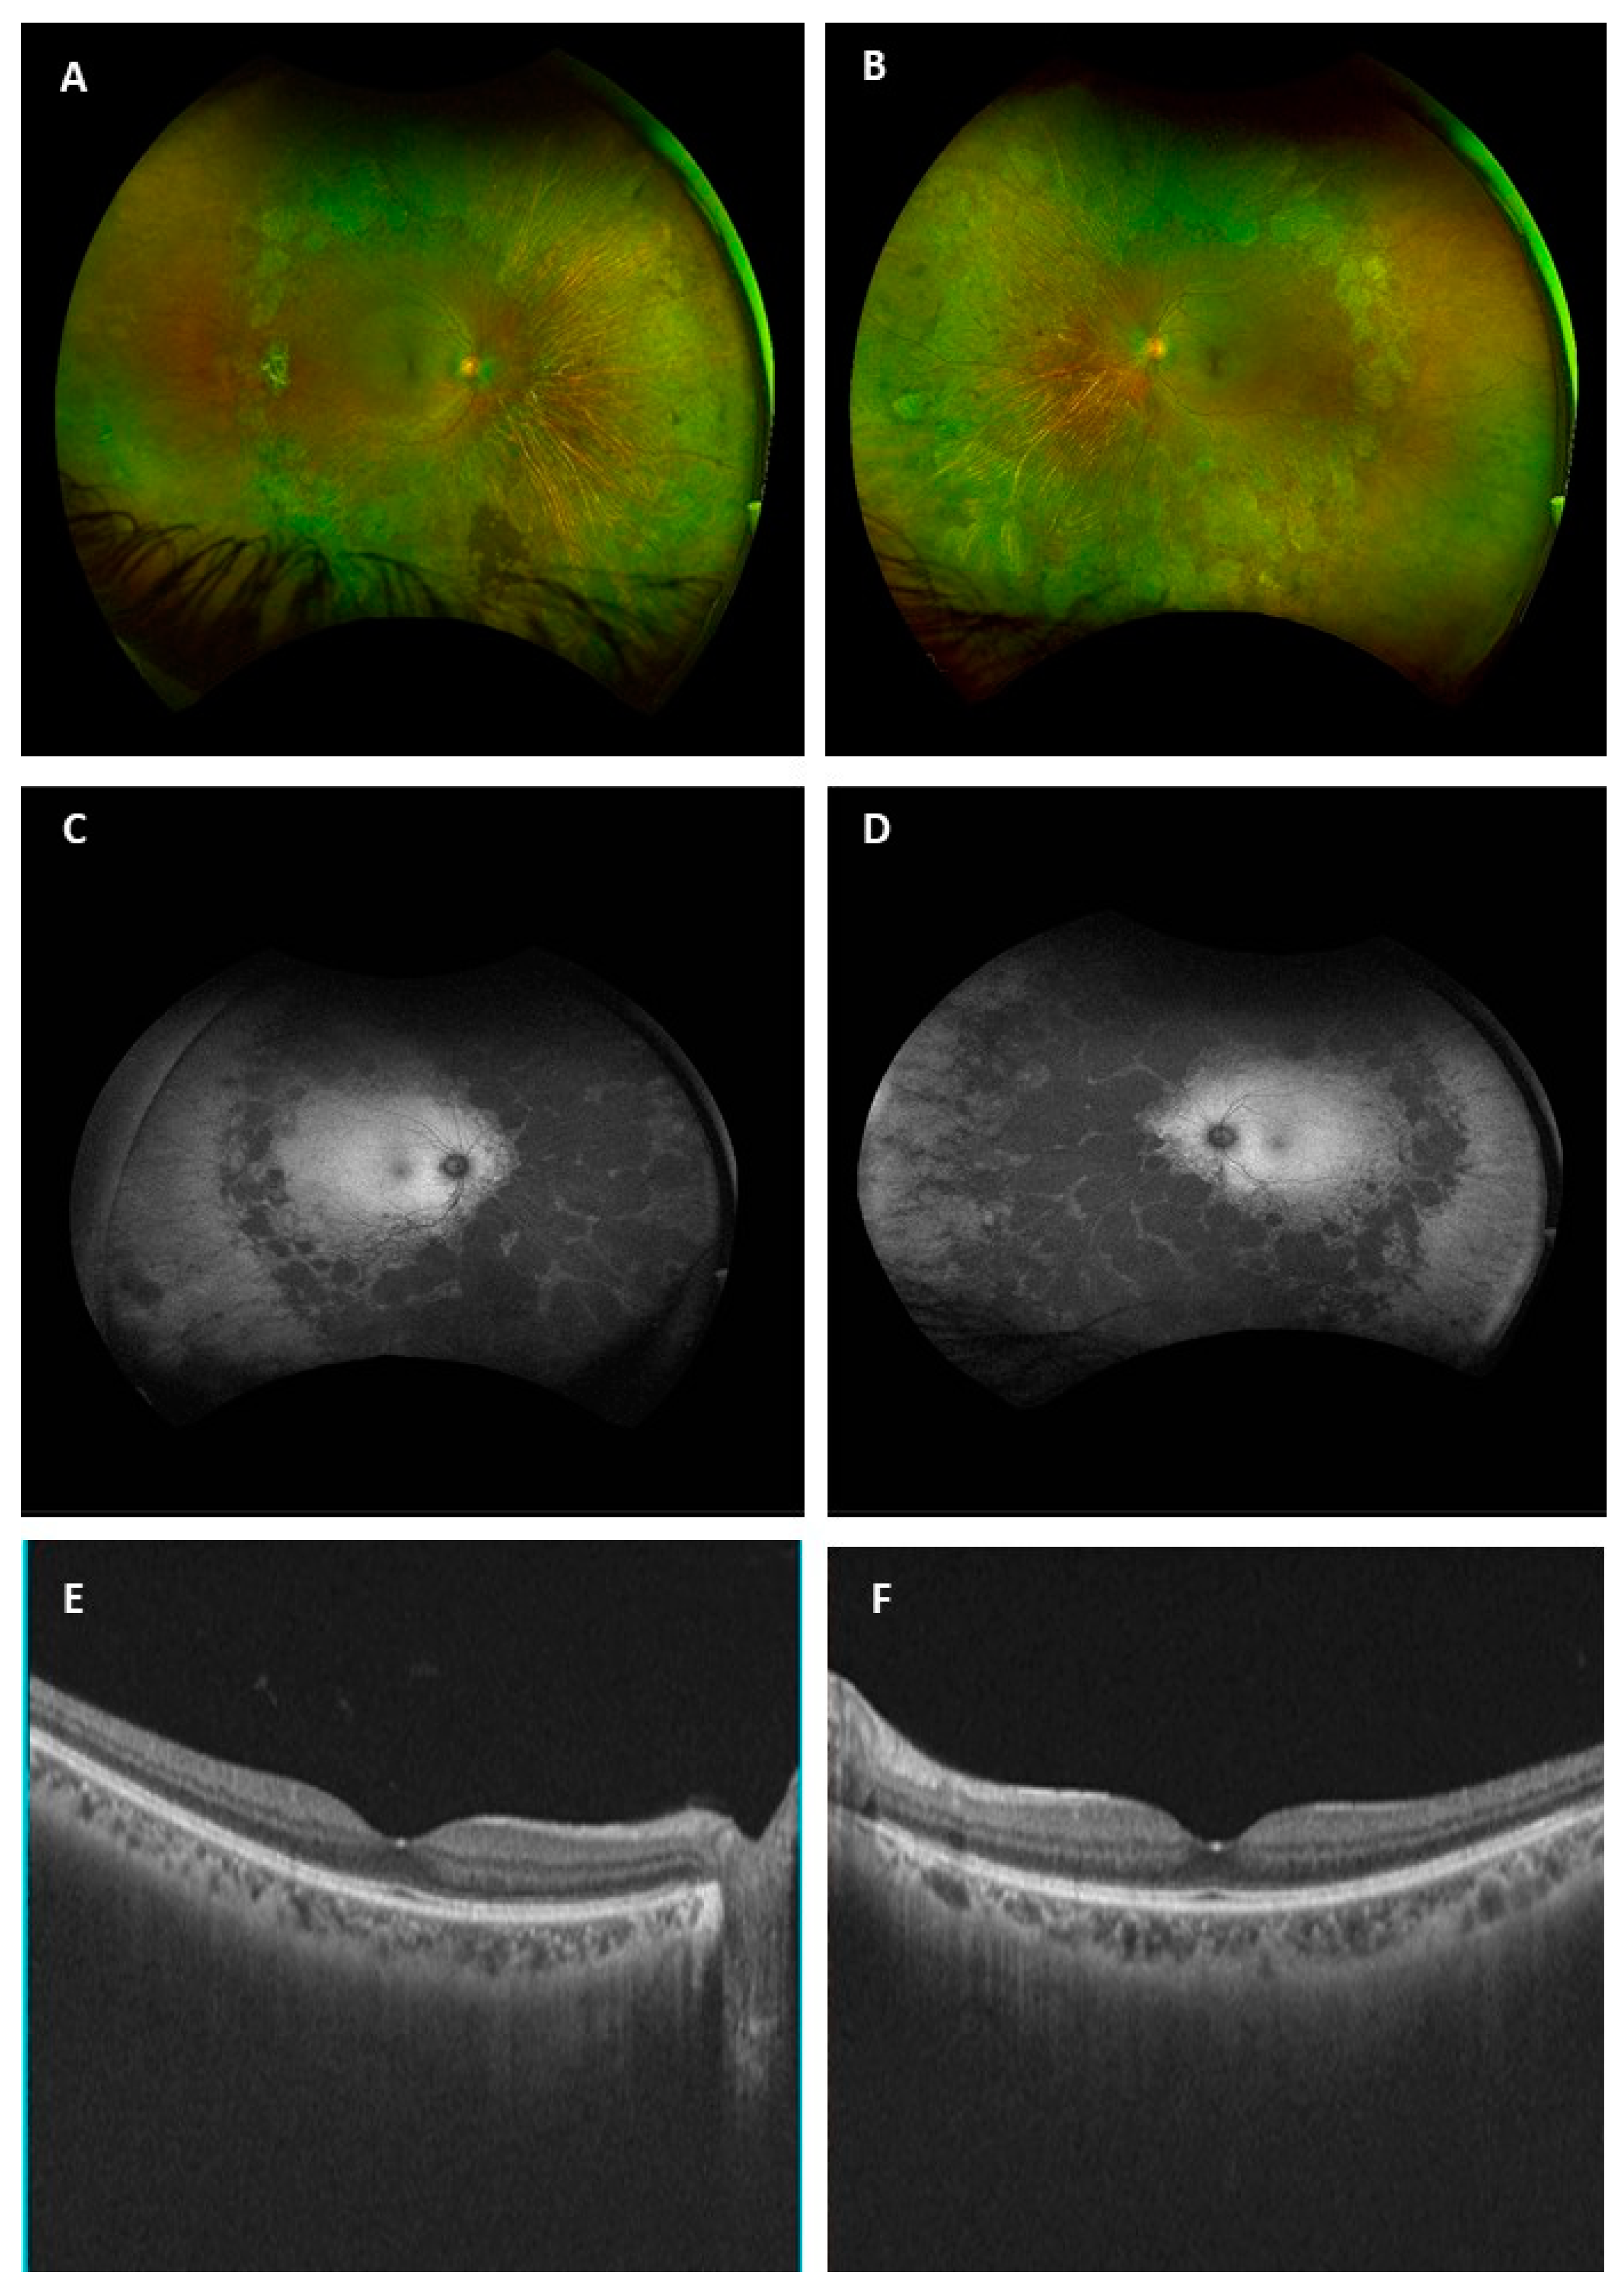

A Rare Case of Didanosine-Induced Mid-Peripheral Chorioretinal Atrophy Identified Incidentally 11 Years after the Drug Cessation

Joharjy, H.; Pisella, P.-J.; Audo, I.; Le-Lez, M.L. A Rare Case of Didanosine-Induced Mid-Peripheral Chorioretinal Atrophy Identified Incidentally 11 Years after the Drug Cessation. Medicina 2022, 58, 735. https://doi.org/10.3390/medicina58060735